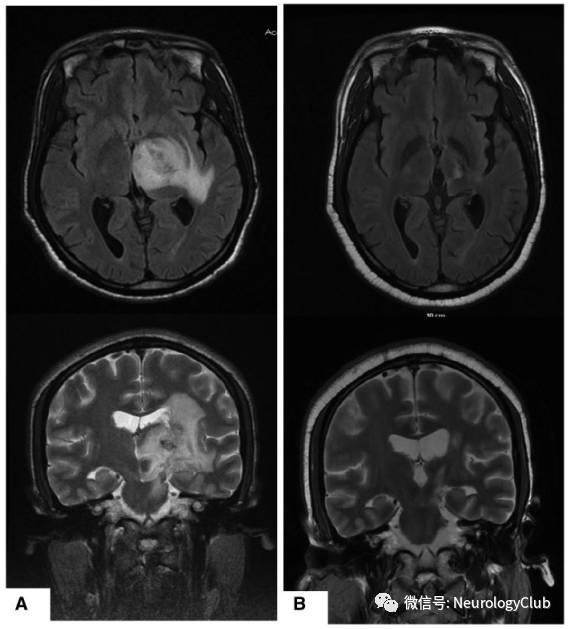

脑实质病变

(图4:FLAIR可见脑桥与中脑受累,延伸累及间脑)

(图9:A:左侧内囊丘脑区假瘤样较大病灶;B:治疗后明显改善)